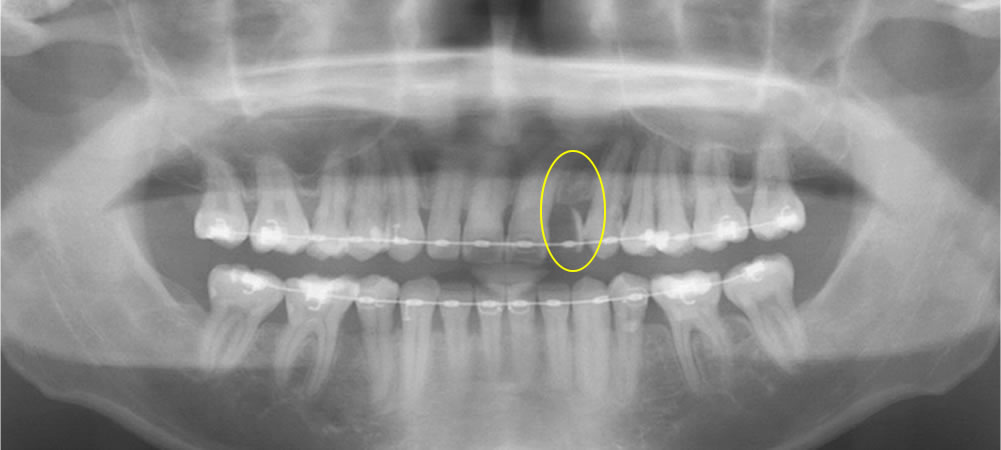

初診時のレントゲン画像

1歯の中間欠損の場合、補綴治療の選択肢としては義歯、ブリッジ、インプラント、接着ブリッジが挙げられます。患者さまは歯を削りたくないとのことから、インプラント治療を希望されました。中間欠損におけるインプラント治療は、両隣在歯の保護(切削量減、負担軽減)の観点から、第一選択と考えられます。